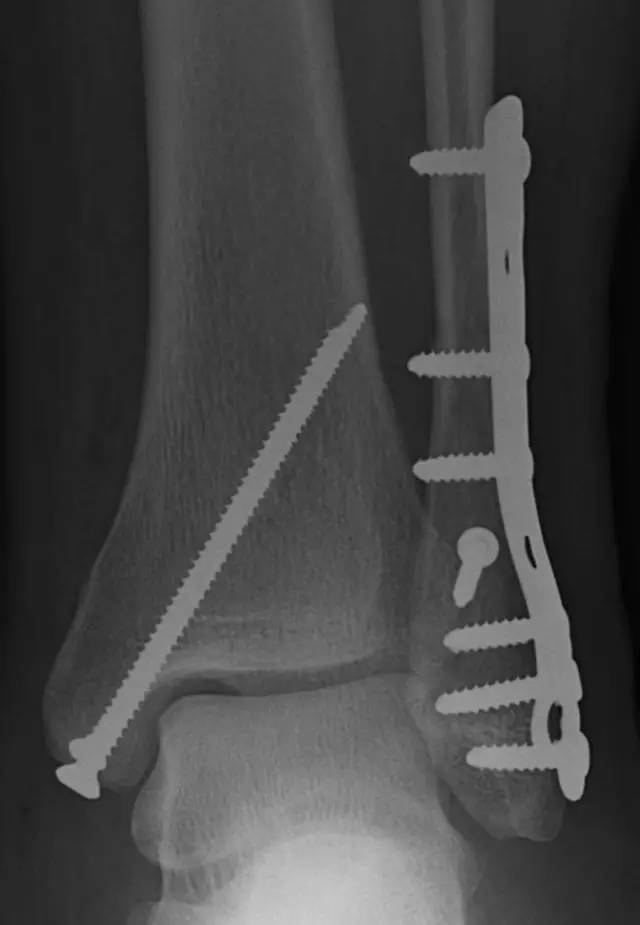

内踝垂直型骨折的手术技巧

推荐的手术方式

结果显示,4 组均导致 2 mm 移位时所需的负荷分别为:180.77 N/mm、68.15 N/mm、163.28 N/mm 和 138.77 N/mm。由此可见,中和钢板,远近端各两枚螺钉的固定方式,稳定性最佳。

虽然单纯的内踝骨折也有通过保守治疗获得良好疗效的报道,但更多的文献还是支持进行手术治疗,尤其对于垂直骨折线的内踝骨折,中和钢板结合加压螺钉的方式更为可取。而 2 枚螺钉固定时,呈「八」字形排列,全螺纹双皮质固定的稳定性最佳。